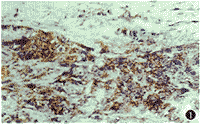

HLA-DR和ICAM-1的阳性表达部位为细胞膜。正常角膜中2例HLA-DR和ICAM-1轻度表达,并且阳性细胞均位于近角巩膜缘上皮基底细胞。病变角膜,尤其是炎性病变、移植排斥反应、化学损伤以及有新生血管伸入的角膜白斑,HLA-DR和ICAM-1阳性细胞增多,可表达于角膜上皮细胞、内皮细胞、基质细胞、巨噬细胞、树突状细胞和淋巴细胞表面(表1,图1,2)。正常角膜和各类病变角膜的HLA-DR、ICAM-1及其两者共同表达的阳性率差异有显著性(P<0.01)。

图1 角膜上皮及基质浅层中有大量炎性细胞浸润,细胞膜明显着色 SP×40